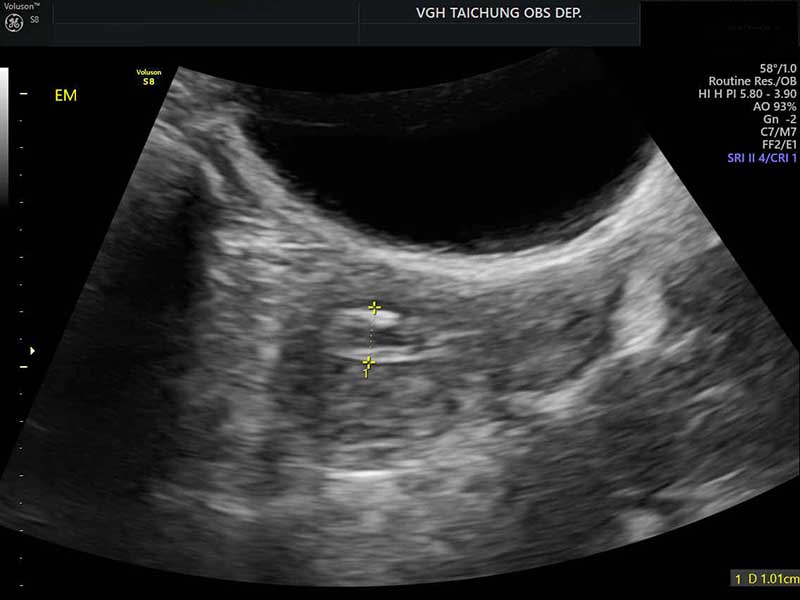

58歲李小姐停經7年後突然出現陰道出血,且持續兩週未止,起初李小姐至診所,超音波檢查發現子宮內膜增厚,先服藥物治療,但出血未改善,轉診至臺中榮總,切片診斷為子宮內膜癌,須手術切除子宮、卵巢及骨盆淋巴腺治療。

孫珞也提醒婦女們,造成停經後出血原因包括:陰道及子宮頸萎縮、息肉或肌瘤等良性原因;子宮內膜亦可能發生異常增生,雖然尚未達到惡性程度但仍需積極手術處理;惡性原因則以子宮內膜癌最為常見,其他還包括子宮頸癌、卵巢癌、陰道或外陰癌。

如果民眾屬子宮內膜癌的高風險群,包括初經早或停經晚、長期月經不規則、肥胖、糖尿病、代謝症候群、曾具多囊卵巢症候群病史、不曾懷孕、使用荷爾蒙治療等狀況,建議應定期接受婦科檢查。停經後子宮內膜癌的患者有90%都會出現陰道出血的症狀,更年期後若有不正常出血,不論出血天數或血量,一定要盡快就醫檢查,才不會錯過治療時機。